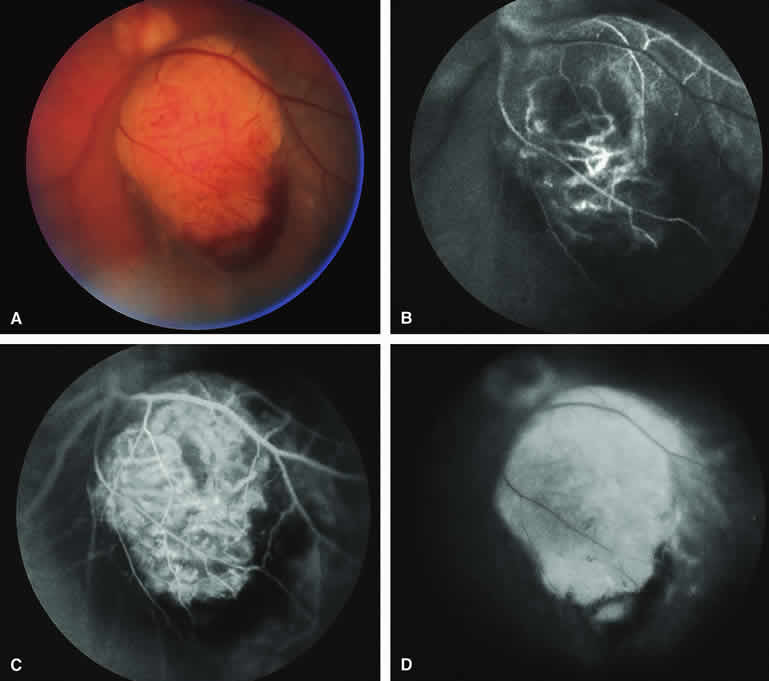

Choroidal Nevus with Drusen and Clumps of RPE Hyperplasia

If a choroidal nevus has drusen and RPE alterations on its surface (see Fig. 4A), fluorescein angiography (Fig. 4B, C, and D) tends to show patchy or stippled window defect hyperfluorescence corresponding to foci of RPE depigmentation, fluorescence blockage by clumps of RPE hyperplasia on the surface of the lesion, and late staining of at least some of the drusen. These features are not usually as evident on ICG angiography as they are on fluorescein angiography.